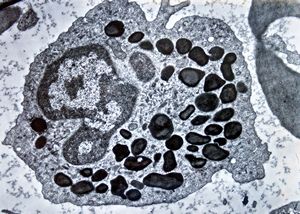

blood - trombocytes

thrombocyte